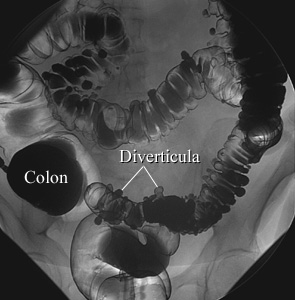

In an air-contrast study, the colon is first filled with barium and

then the barium is drained, leaving only a thin layer of barium on the wall of

the colon. The colon is then filled with air. This barium enema image shows

pouches (called diverticula) in the wall of the colon.